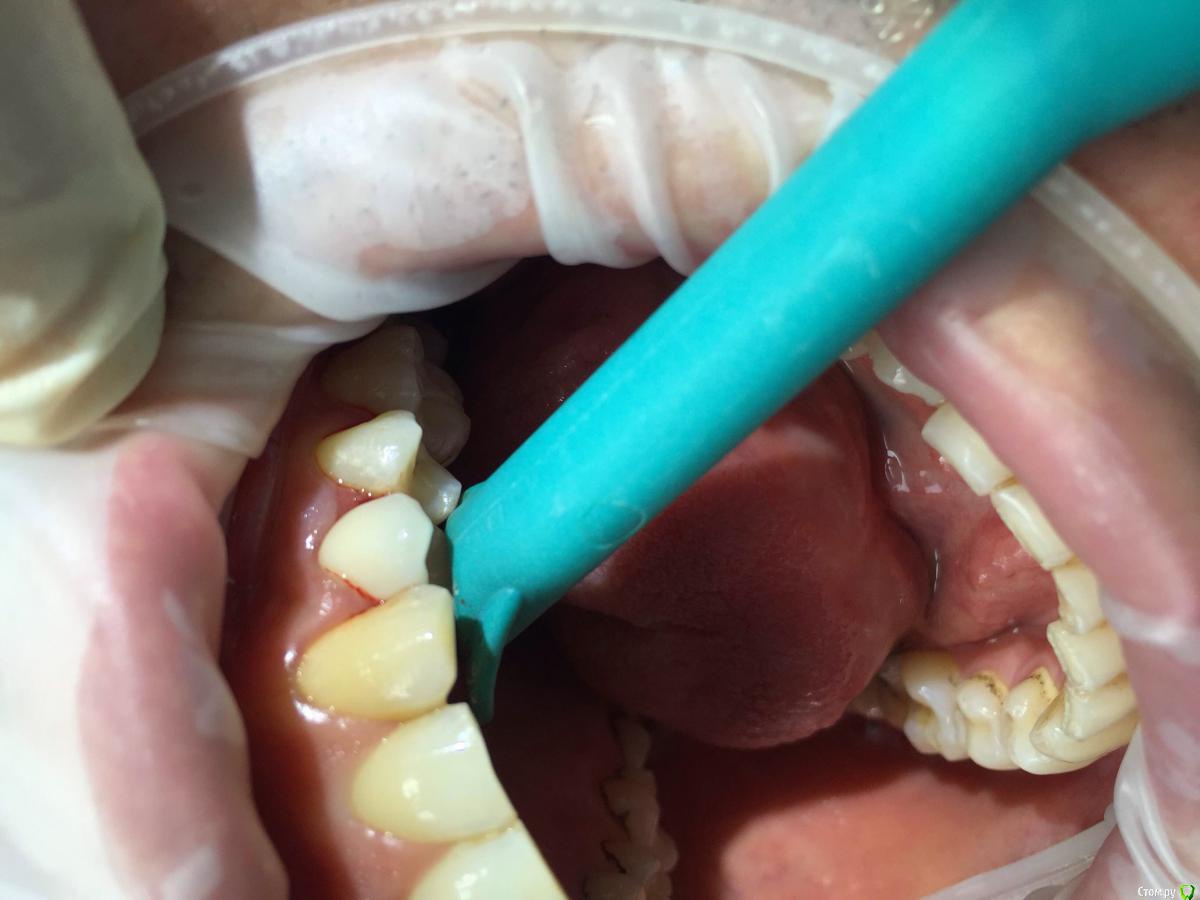

Вандышев Дмитрий Опубликовано 25 августа, 2015 Поделиться Опубликовано 25 августа, 2015 Подскажите .Десневой сосочек между 2.4и2.5 постоянно кровоточит при легком прикосновении.Имплант устанавливал 2.4 одномоментно с удалением и постановкой временной коронки.С временной коронкой кровоточивость была чуть меньше,после постановки постоянной коронки прошло 4-5месяцев и кровоточит практически всегда при прикосновении.Контактные пункты между 2.3и2.4и2.5 плотные.Зонд между 2.4и2.5 проваливается на 5-6мм,сосочек начинает уходить.Сосочек между 2.3и2.4 не кровоточит Ссылка на комментарий

hemchik Опубликовано 25 августа, 2015 Поделиться Опубликовано 25 августа, 2015 (изменено) может травмирует во время чистки зубов. там на 25 мезиально пломба? цемента вроде не видно Изменено 25 августа, 2015 пользователем hemchik Ссылка на комментарий